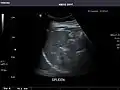

Spleen

Spleen: Normal in size.